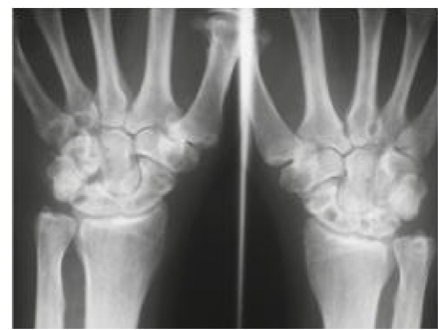

Dx diferencial

Si el depósito incrementa y es: oligo o poliarticular

• ARP

• AR seronegativa